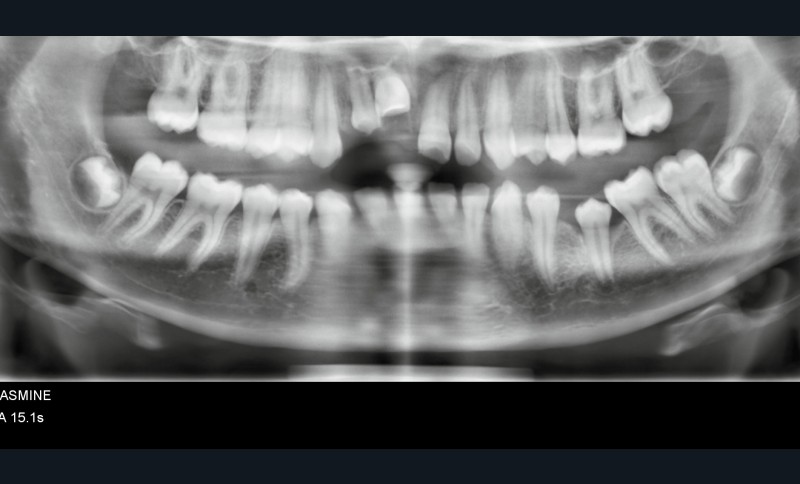

Yasmine, une adolescente de 14 ans et demi, en bonne santé générale, consulte en urgence vers 10h30, à la suite d’une chute s’étant produite le matin même en allant à l’école vers 8h. Les figures 1 et 2 montrent respectivement les vues cliniques et radiographiques. La mère nous rapporte un antécédent de trauma sur les incisives centrales, il y a quelques années.